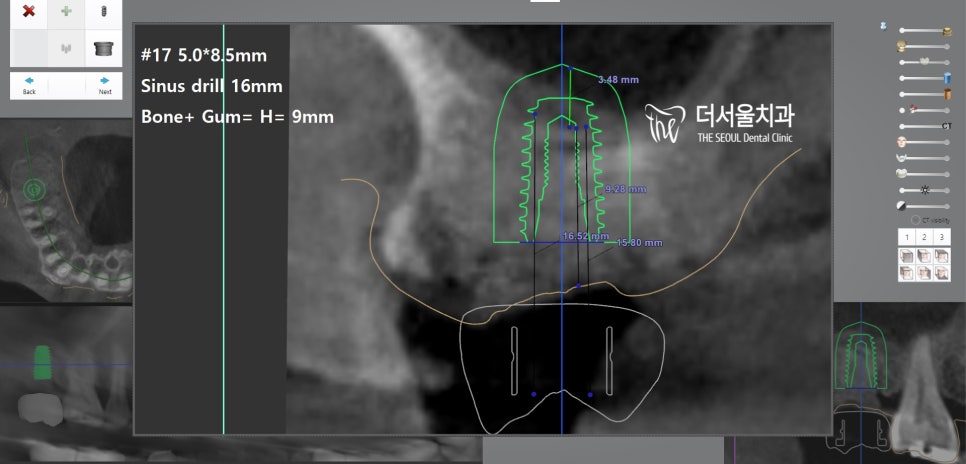

『 단, 여기서 꼭 살펴봐야 될 것이 있죠? 』

바로 상악동, 뿌리와의 거리인데요.

상악동의 함기화로 인해

충분한 치조골이 보장되지 않고

줄어들어 있는 것을 볼 수 있습니다.

따라서 성남치과 에서는 부작용 없는

상악동 거상술 및 뼈이식을 동반한

임플란트 식립을 통해 잃어버린

구강 내 기능을 회복시키는 것으로 계획을 세웠죠.

컴퓨터 분석으로 픽스처 위치까지

확실하게 확인을 한 뒤에

본격적인 수술 과정으로 들어갔는데요.